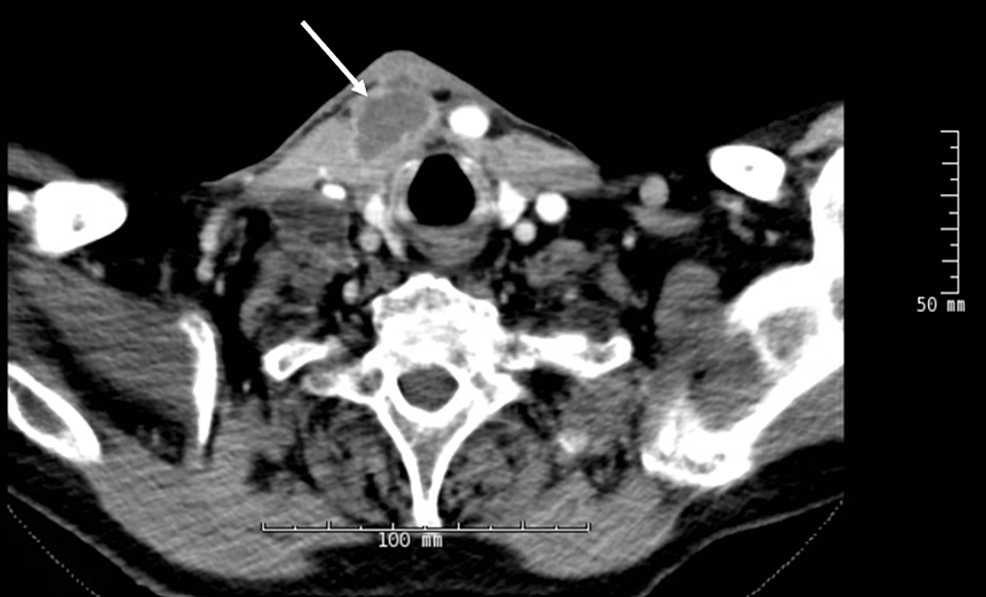

Immune Reconstitution Inflammatory Syndrome Reaction in Patient on Long-Term Prednisone

Immune reconstitution inflammatory syndrome (IRIS) can be triggered in many ways. IRIS has been recognized during tuberculosis (TB) therapy, especially in patients newly initiated on antiretroviral therapy for HIV or...

Immune reconstitution inflammatory syndrome (IRIS) can be triggered in many ways. IRIS has been recognized during tuberculosis (TB) therapy, especially in patients newly initiated on antiretroviral therapy for HIV or those taken off immunosuppressives such as tumor necrosis factor-alpha inhibitors. However, there are still many triggers of...